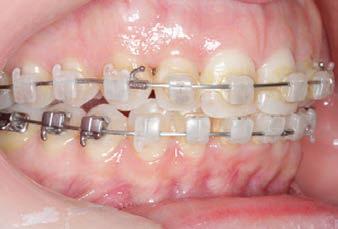

CLASS II DIV.1 - Marra

PROVIDED BY: DR. LUIS CARRIÈRE

INITIAL - 4/4/18

PROGRESS 1 - 26/9/18 - Class I platform accomplished in 5.75 months with Motion 3D COLOR Appliance

PROGRESS 2 - 26/9/18 - Placement of the SLX 3D Clear Brackets

[CONTINUED ON NEXT PAGE]

with M-ONE .015 Cu Nitanium 27°

PROVIDED BY: DR. LUIS

PROGRESS 3 - 30/10/18 - With M-TWO .020 x .020 Cu Nitanium 35° archwire

PROGRESS 4 - 27/11/18 - 3 links power chain: 5, 4, bypass 3 to crimp hooks

PROGRESS 5 - 13/3/19 - With M-TWO .020 x .020 Cu Nitanium 35° archwire

PROGRESS 6 - 1/8/19 - With M-THREE.019 x .025 Beta Titanium wire

52 HENRY SCHEIN ORTHODONTICS

FINAL - 10/10/19 - Appliances removed AFTER

PROGRESS 7 - 10/10/19 - Final day in SLX 3D Clear Brackets BEFORE